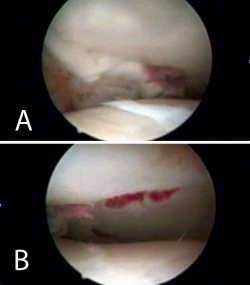

Nos colocamos sentados frente al miembro lesionado, elevando la mesa quirúrgica con la pantalla de la torre de artroscopia frente a nosotros. Tras realizar los portales de artroscopia, procedemos a un lavado exhaustivo de la articulación dejando introducir el suero de la bolsa de artroscopia (no utilizamos bomba de presión) hasta que dejen de salir restos de hematoma por el aspirador de artroscopia. A continuación, introducimos el sinoviotomo y resecamos el hemartros fracturario hasta que identifiquemos los fragmentos del foco de fractura (Figuras 4 y 5).

Figura 4. Caso 1: fractura tipo B2 (fractura-depresión o split fracture). Posición del cirujano y del paciente; colocación del monitor de radioscopia y de artroscopia.

Figura 5. Lavado exhaustivo. Desbridamiento del hemartros y limpieza articular.

Figura 8. Percusión del fragmento con el impactor, control radioscópico de la posición del impactor e imagen artroscópica del escalón articular antes de la reducción.

Figura 9. Imagen artroscópica de la reducción del fragmento hundido y del trazo articular.

Figura 10. Colocación de los tornillos. Control radioscópico.

Figura 11. Control radiológico anteroposterior y lateral.